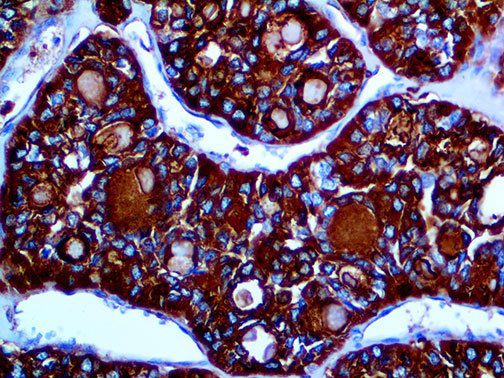

It is the ICU physician who is most likely to witness one of the deadliest manifestations of the abnormal immunological response, the cytokine storm syndrome (CSS). This response is also referred to by some as the cytokine release syndrome (CRS). CSS is characterized by continuous activation and expansion of macrophage and lymphocyte populations, which secrete large amounts of cytokines, causing the cytokine storm. This massive cytokine release is akin to hemophagocytic lymphohistiocytosis (HLH) disease, a syndrome characterized by initial unchecked and persistent activation of cytotoxic T lymphocytes and NK cells.

Clinical and laboratory manifestations of HLH include fever, enlarged liver and/or spleen, neurologic dysfunction, coagulopathy, liver dysfunction, cytopenias (i.e., low levels of erythrocytes, leukocytes, and/or platelets), hypertriglyceridemia, hyperferritinemia, hemophagocytosis, and eventually diminished NK cell activity as the immune system becomes progressively paralyzed. HLH can be familial (primary HLH) or secondary to another disease process (sHLH), such as rheumatic disease, in which it is referred to as macrophage activation syndrome (MAS, characterized by elevated ferritin).